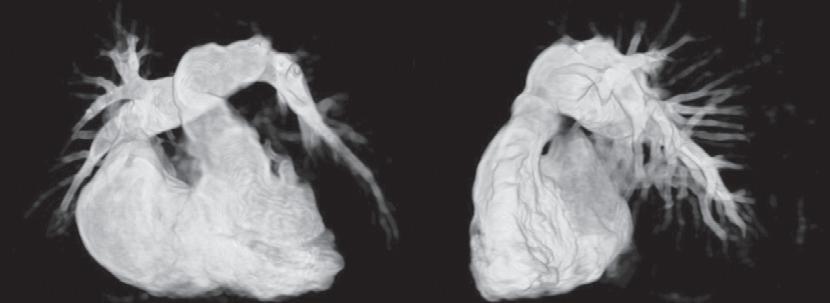

E-FIGURE 1-1 Devices that are increasingly available to provide assistance during high-risk percutaneous coronary intervention (PCI) include percutaneous extracorporeal circulatory support devices such as (A, B) the TandemHeart and (C) the Impella device. (A) The TandemHeart removes oxygenated blood from the left atrium and returns this blood into the peripheral arterial circulation; with the (B) aid of a centrifugal pump. C, The Impella left ventricular assist device is a miniaturized rotary blood pump that is placed retrograde across the aortic valve, and it aspirates (inlet area) up to 2.5 L/min of blood from the left ventricular cavity and subsequently expels this blood (outlet area) into the ascending aorta. (From Valgimigli M, Steendijk P, Serruys PW, et al: Use of Impella Recover LP 2.5 left ventricular assist device during high-risk percutaneous coronary interventions; clinical, haemodynamic and biochemical findings. EuroIntervention 2[1]:91-100, 2006; and Vranckx P, Meliga E, De Jaegere PP, et al: The TandemHeart, percutaneous transseptal left ventricular assist device: a safeguard in high-risk percutaneous coronary interventions. The six-year Rotterdam experience. EuroIntervention 4:331, 2008.)